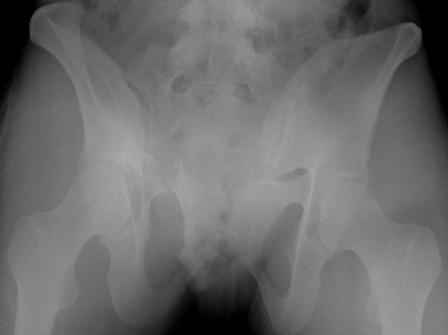

думаю, для начала необходимо определиться с типом перелома. Для этого, как минимум необходима проекция inlet, дальше часть вопросов может отпасть сама-собой.

Конечно важен механизм травмы, на первый взгляд возможно двустороннее повреждение задних отделов.

для принятия решения вход, выход из малого таза и кт задних отделов

Больную нужно дообследовать- inlet, outlet, боковые проекции таза 3/4, КТ таза, таз 3D.